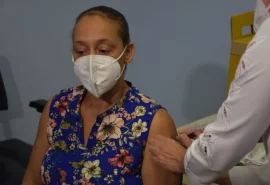

Drive-thru vacina idosos com mais de 80 anos contra a Covid-19 neste sábado (27)

'Drive thru' vacina 1.100 idosos com mais de 85 anos neste fim de semana

Vacinação de idosos acamados começa nesta segunda-feira (15)

Bauru terá vacinação 'drive thru' para idosos acima de 85 anos

Doria acompanha início da vacinação drive-thru de idosos a partir de 90 anos

Idosos acima de 90 anos começam a ser vacinados em Bauru

Bauru inicia vacinação de idosos acima dos 90 anos na próxima segunda-feira (08)

Estado de SP inicia vacinação de idosos acima de 85 anos de idade em fevereiro

Secretaria de Saúde inicia vacinação dos profissionais da 'linha de frente' em Bauru